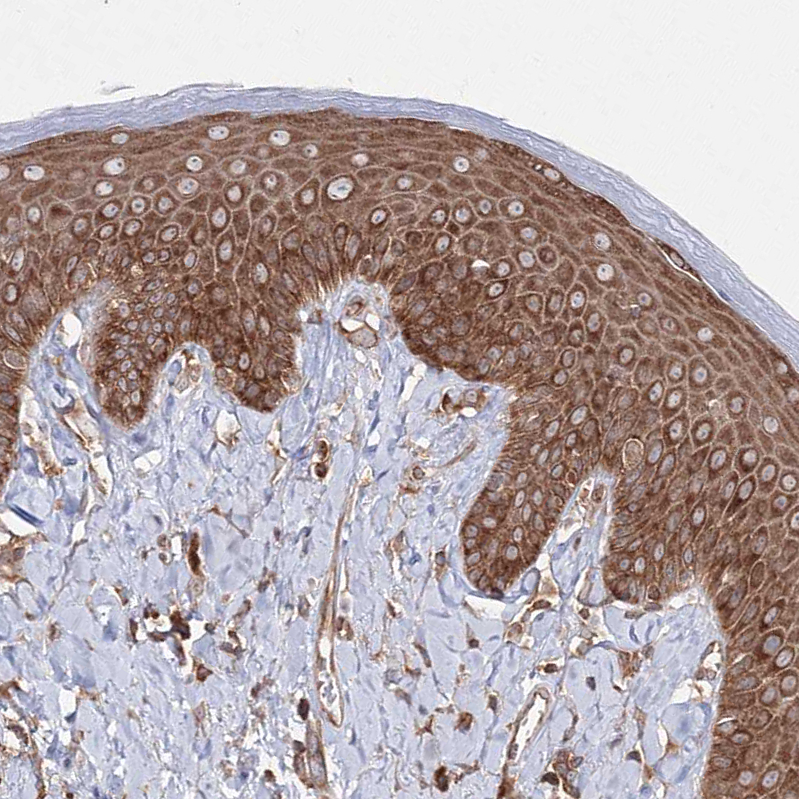

Immunohistochemical staining of human cerebral cortex shows cytoplasmic positivity in neuronal cells.